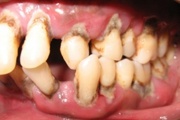

GAgP kahjustused 19 aastasel patsiendil